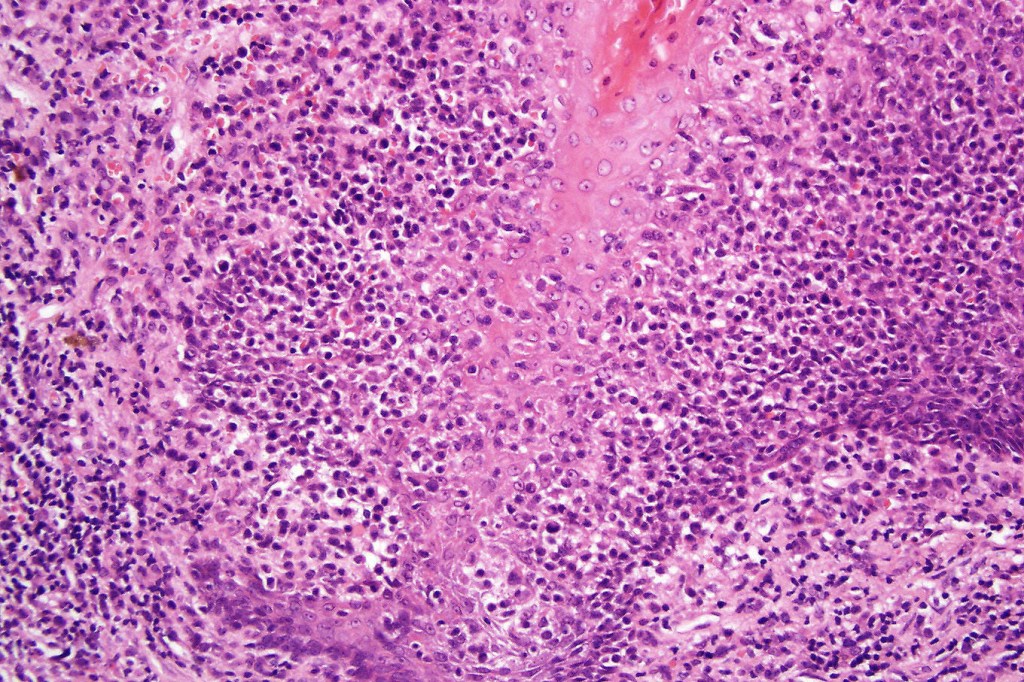

Histological features

•Follicular infiltration by atypical lymphocytes & Sézary cells

•Eosinophils sometimes conspicuous (eosinophilic folliculitis-like appearance)

•Granulomatous inflammation secondary to follicular destruction

•Large cell transformation occasionally present